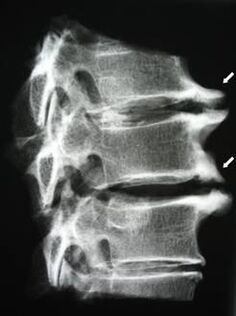

Aux premiers stades, l'ostéochondrose est détectée par IRM. Par la suite, la pathologie peut être diagnostiquée par radiographie. Sur les radiographies de la colonne cervicale, une diminution de la distance entre les vertèbres, des modifications pathologiques des facettes articulaires et une ostéophytose deviennent évidentes.